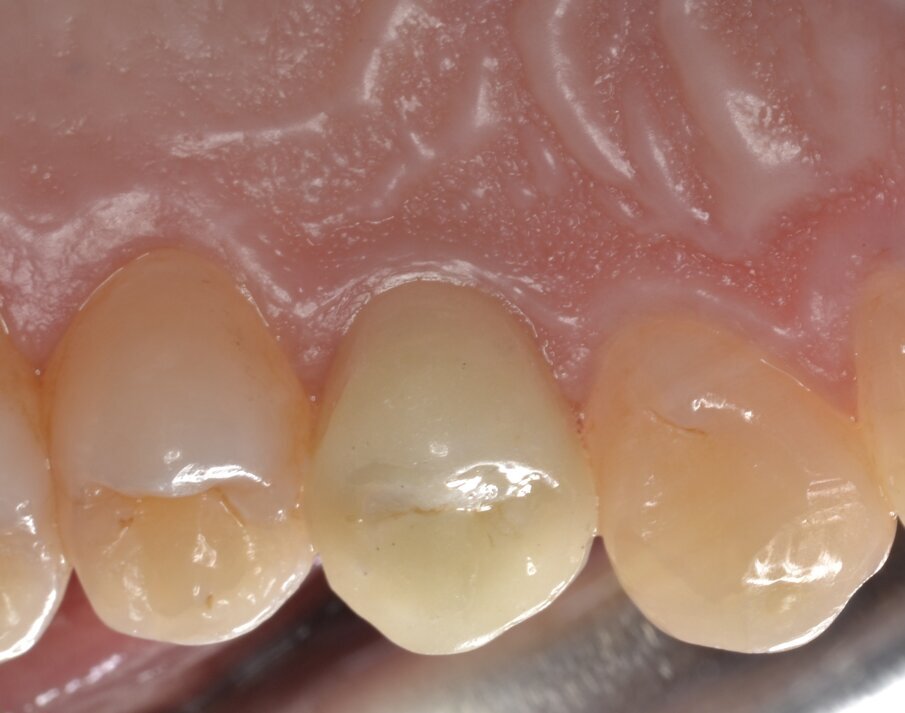

Dopo aver opportunamente preparato un abutment definitivo che sia idoneo per altezza e forma del segmento transmucoso, si procede alla cementazione di una corona protesica definitiva in zirconia stratificata. Le immagini del follow-up a 12 mesi (Figg. 23-25) e il contestuale controllo radiografico endorale (Fig. 26) indicano un’ottima risposta dei peri-implantari tessuti duri e molli.

Fig. 23 - Corona protesica definitiva in zirconia stratificata (visione buccale).

Fig. 24 - Corona protesica definitiva in zirconia stratificata (visione occlusale).

Fig. 25 - Corona protesica definitiva in zirconia stratificata (visione orale).